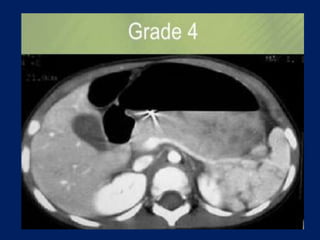

This document discusses imaging of the spleen and summarizes various congenital anomalies and pathologies that can affect the spleen. Some common congenital anomalies mentioned include accessory spleens, asplenia, polysplenia, and splenic fusions. Acquired conditions like repeated infarctions, infiltration, tumors, and cysts can also cause splenomegaly or functional asplenia. Wandering spleen is discussed as a rare congenital anomaly where the spleen lacks attachments and is mobile within the abdomen. Various grades of splenic lacerations and examples of splenic imaging findings are also briefly summarized.